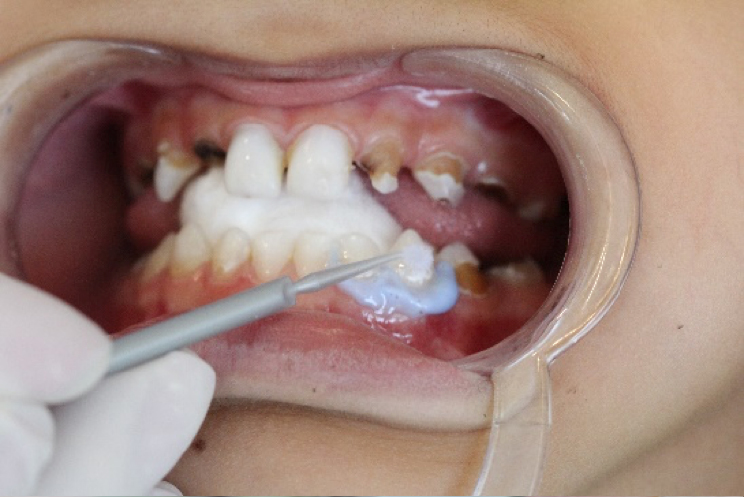

Logo após, perfurou-se a cápsula verde com o microaplicador verde com movimentos circulares e aplicado o produto em quantidade generosa, até que o produto esbranquiçado ficasse transparente. (foto 12, 13, 14)

O paciente foi observado por 30 minutos após o procedimento, e os elementos não apresentaram nenhuma alteração de cor. Após 7 dias o paciente retornou para acompanhamento e novamente nenhuma alteração de cor foi observada. (foto 15)